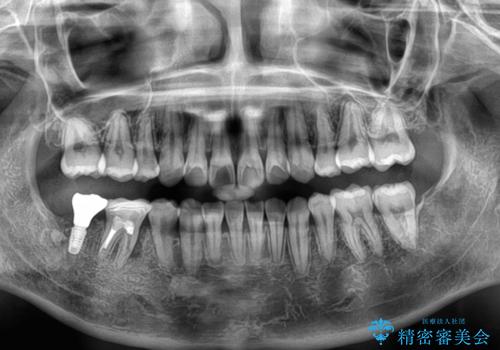

埋伏している右下第二大臼歯は、牽引して咬合に参加させることで計画しましたが、癒着などにより移動困難な場合には、抜歯の上インプラント補綴治療を行うこととしました。

右下の埋伏歯はやはり癒着しており、抜歯の後にインプラントを埋入することとなりました。

埋伏歯の牽引や、奥歯の咬み合わせ改善、インプラント補綴治療と治療期間が延びてしまう要素が多く、治療は難航しましたが、最終的に非常に満足のいく仕上がりとなりました。